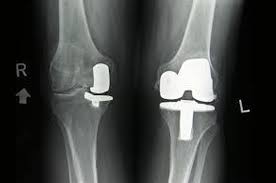

The company ORTHOPEDIC NIKIFOROV was founded in 1998 by the candidate of medical sciences. doctor of orthopedic-traumatologist of the highest category Nikiforov IA Owing to high professionalism and results of work, ORTONIC has gained well-deserved reputation and reputation among colleagues and population of Dnepropetrovsk region and CIS countries (Russia, Moldova, Armenia, etc.). The principle of the enterprise is NO IMPOSSIBLE, it is based on knowledge, experience and active implementation of modern technologies in orthopedics and traumatology. Conservative methods of treatment include individual selection of medicines, therapeutic blockades, manual therapy, massage, physiotherapy (vibration table, magnetotherapy, bioptron, electromyostimulation, etc.), rehabilitation with the suggestion of the necessary concomitant devices and means for the fastest recovery (corsets, bandages, various joint fixators, crutches, walking sticks, etc.). Various minor invasive interventions (chymonucleolysis, vertebroplasty, kyphoplasty, percutaneous nucleoplasty using cold plasma) that are performed on an outpatient basis are successfully used to treat problems associated with spine pathology. The latest modern treatment methods introduced in our company are endoscopic operations using the TYSSES technique of Joimax (Germany) with intervertebral hernias, stenosis and other pathologies of the spine, which allow to avoid complications occurring during open operations and the accompanying general anesthesia. We have many years of successful experience in traditional and modern minimally invasive endoprosthetics of large and small joints, which remains the main direction of our activity. Our company is the exclusive representative of the German company IO International Orthopaedics Holding GmbH, which based on the already known prostheses, its ideas and technological capabilities, has developed and implemented a new concept in hip replacement - an artificial joint prosthesis (ICON). We assist interested colleagues in training the operative technique for installing an artificial joint prosthesis - ICON, both in the workplace and in Germany. For 20 years we have been successfully cooperating with Sanitatshaus Gerd Klinz ortho team, an enterprise that for 20 years has been one of the leading places in Germany for the production of functional prostheses of the upper and lower limbs, as well as cosmetic prostheses of limbs and other body parts (nose, ears, eyeballs, fingers). We have an atmosphere of friendliness and human participation. Politeness, benevolence, the desire to understand and help is the basis of our attitude towards patients. We are always glad to see you and will do our best to make you feel great! We are waiting for you at: Ukraine, Dnepr, Gagarin Ave., 13 (under reconstruction) on all questions to address: tel .: +38 (050) 488-88-92 E-mail: orthonik.ukr@gmail.com Germany, Spine Nano Klinik, Zeppelinstr. 21, Potsdam Tel. +4901801121919 E-mail: kmw.nikiforov@hotmail.de